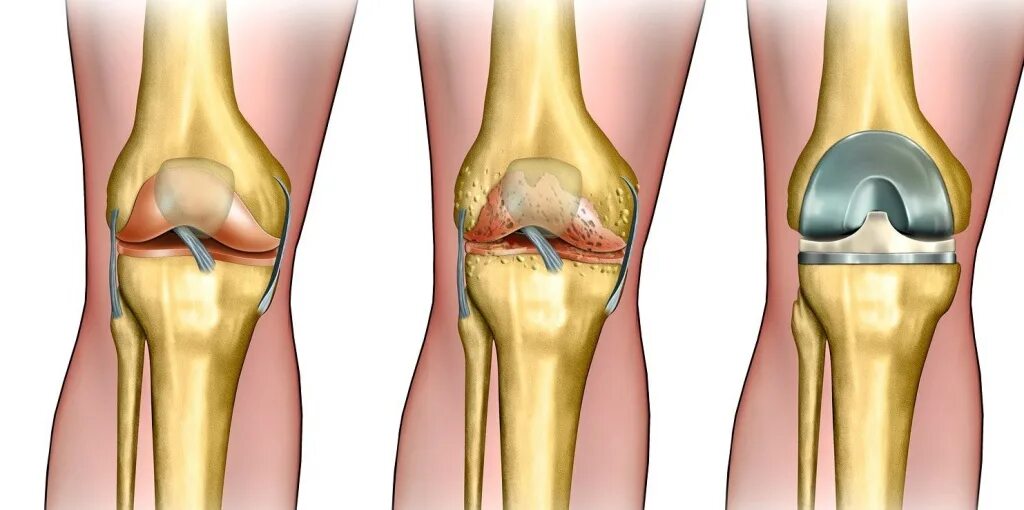

Эндопротез тазобедренного сустава мкб 10